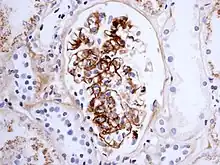

Morphology

Histologically, IgA nephropathy may show mesangial widening and focal and segmental inflammation. Diffuse mesangial proliferation or crescentic glomerulonephritis may also be present. Immunofluorescence shows mesangial deposition of IgA often with C3 and properdin and smaller amounts of other immunoglobulins (IgG or IgM). Early components of the classical complement pathway (C1q or C4) are usually not seen. Electron microscopy confirms electron-dense deposits in the mesangium that may extend to the subendothelial area of adjacent capillary walls in a small subset of cases, usually those with focal proliferation.

The disease derives its name from deposits of immunoglobulin A (IgA) in a granular pattern in the mesangium (by immunofluorescence), a region of the renal glomerulus. The mesangium by light microscopy may be hypercellular and show increased deposition of extracellular matrix proteins. In terms of the renal manifestation of Henoch–Schönlein purpura, it has been found that although it shares the same histological spectrum as IgA nephropathy, a greater frequency of severe lesions such as glomerular necrosis and crescents were observed. Correspondingly, HSP nephritis has a higher frequency of glomerular staining for fibrin compared with IgAN, but with an otherwise similar immunofluorescence profile.[4]

For an adult patient with isolated hematuria, tests such as ultrasound of the kidney and cystoscopy are usually done first to pinpoint the source of the bleeding. These tests would rule out kidney stones and bladder cancer, two other common urological causes of hematuria. In children and younger adults, the history and association with respiratory infection can raise the suspicion of IgA nephropathy. A kidney biopsy is necessary to confirm the diagnosis. The biopsy specimen shows proliferation of the mesangium, with IgA deposits on immunofluorescence and electron microscopy. However, patients with isolated microscopic hematuria (i.e. without associated proteinuria and with normal kidney function) are not usually biopsied since this is associated with an excellent prognosis. A urinalysis will show red blood cells, usually as red cell urinary casts. Proteinuria, usually less than 2 grams per day, also may be present. Other renal causes of isolated hematuria include thin basement membrane disease and Alport syndrome, the latter being a hereditary disease associated with hearing impairment and eye problems.